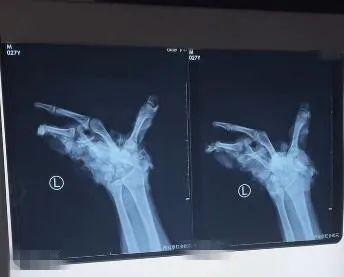

2月5日傍晚,一位来自陕西安康的27岁男子被家人紧急送到西安市红会医院。受伤男子的家属表示,当天下午,这名男子在家放炮仗时,不慎将左手炸伤。

据了解,事发当时,这名男子左手拿了两个“雷子”,本想着点燃一个扔一个,没想到用打火机点燃第一个的时候,不小心引燃了第二个,虽然第一个扔了出去,但第二个却在手中炸开......

事发后,家属紧急将受伤男子送往西安接受治疗。

接诊后,医生发现患者出血严重,左手腕部以及手部软组织和骨质毁损缺损,肌腱及骨质断端外露,污染严重,需要紧急进行手术。

西安红会医院手外科二病区主治医生李鹏:“患者手部伤情严重,没有再植条件。”

目前,受伤男子已进行了截肢手术,还在进一步治疗中。